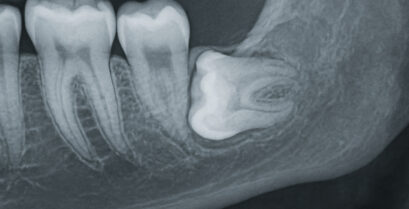

先端の治療方法で「破折歯」を抜歯することなく保存します。